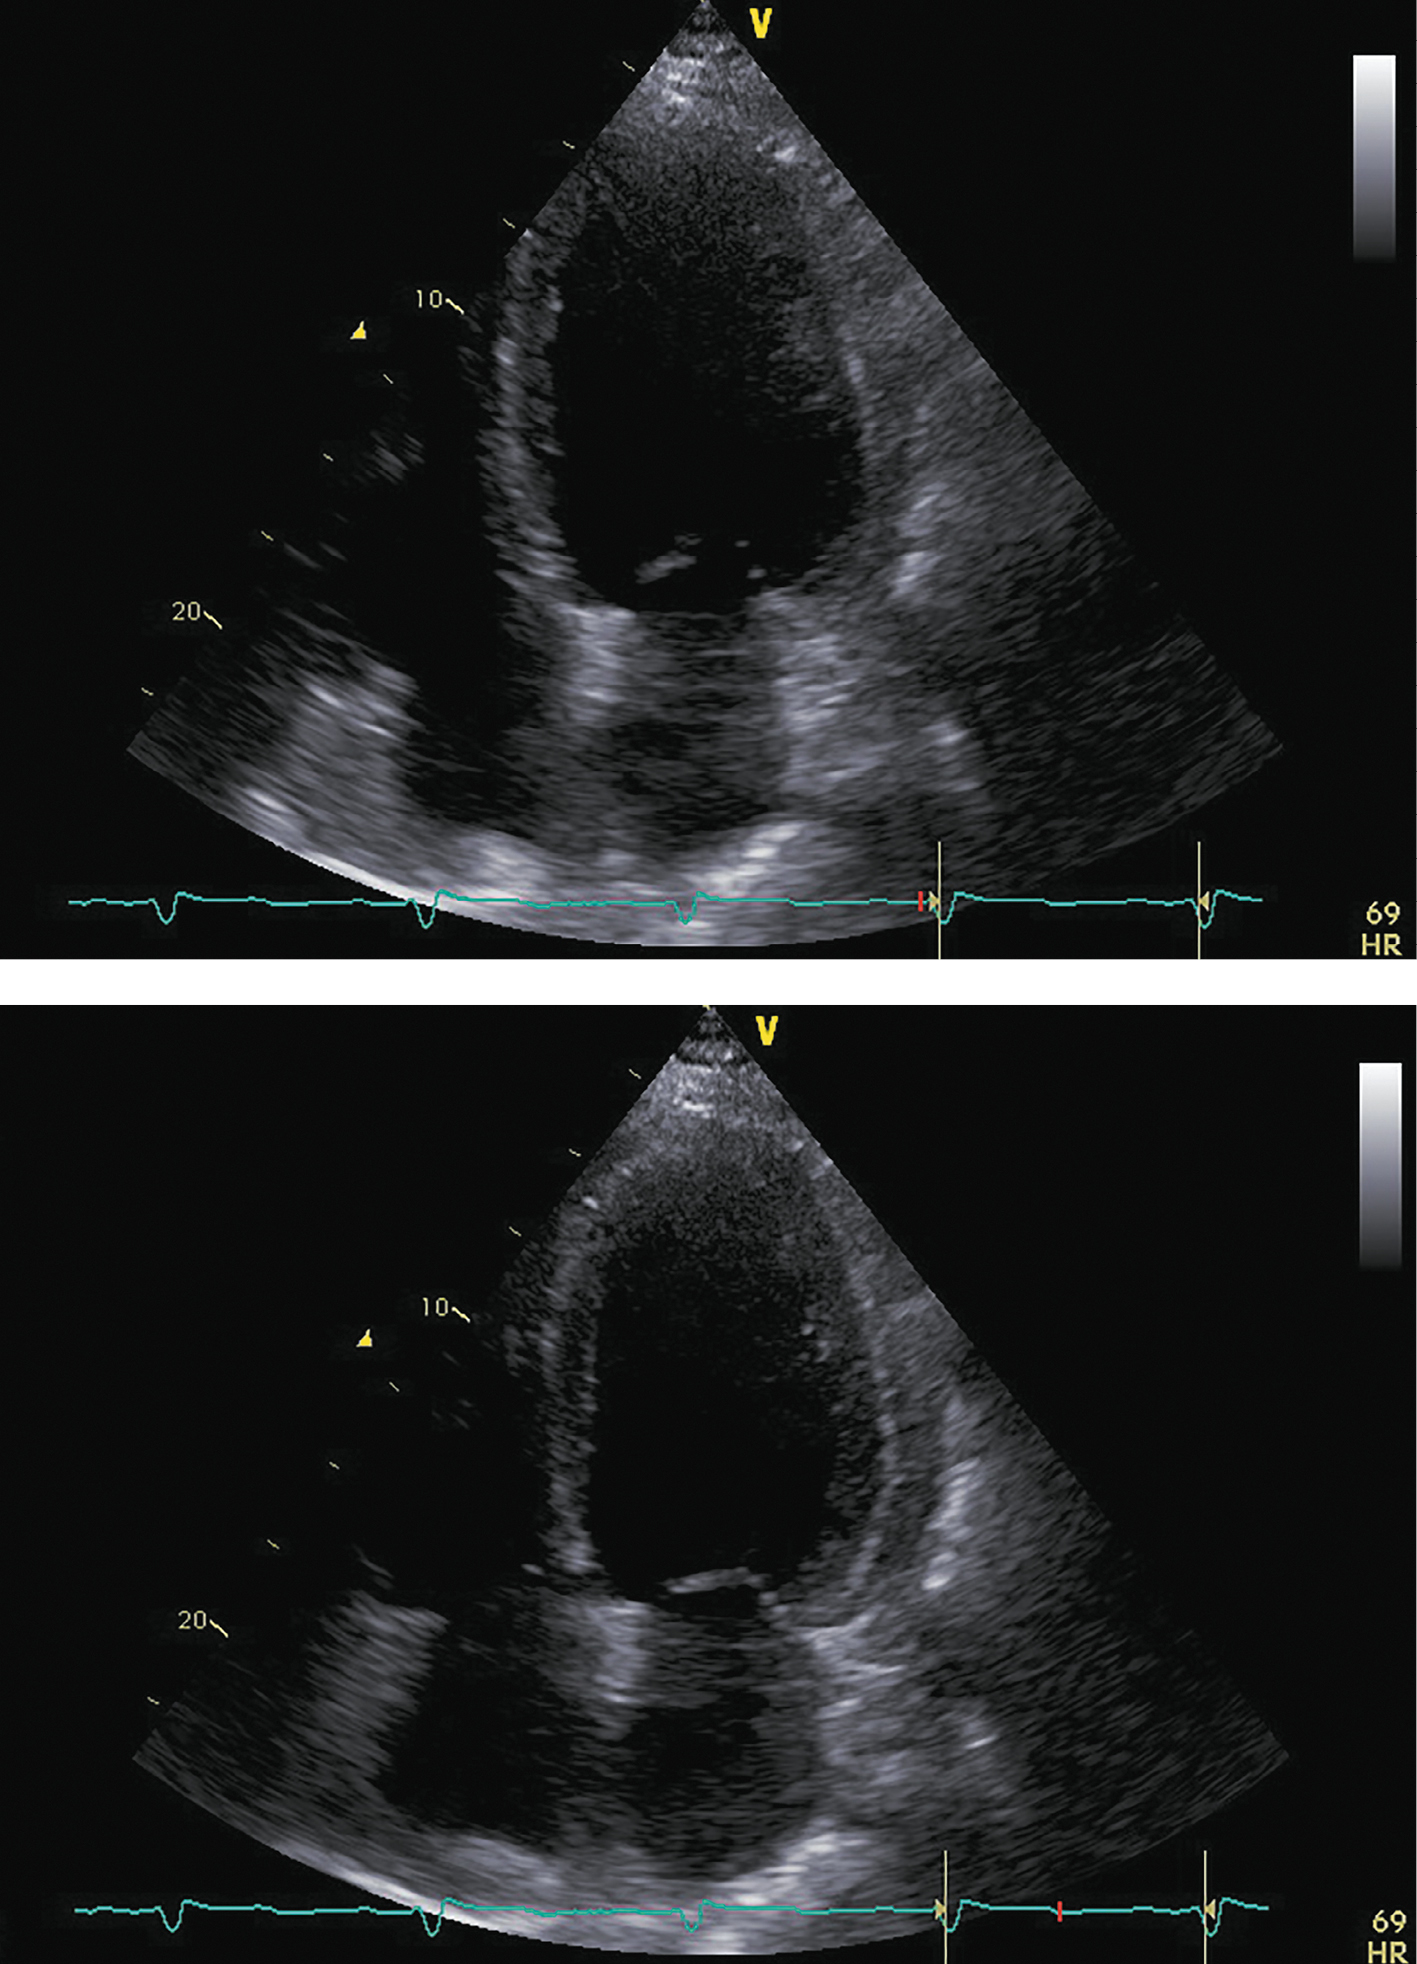

В ноябре 2017 г. пациент госпитализирован повторно для проведения нейрохирургического лечения. Пациент указал, что принимал предписанную терапию в полном объеме. Каких-либо нежелательных лекарственных реакций не выявлено. На фоне лечения симптомы ХСН заметно регрессировали, толерантность к физическим нагрузкам возросла до уровня II ф.к. по NYHA. Физикальной симптоматики легочного застоя и увеличения печени не отмечалось. При контрольной ЭХОКГ (рис. 5; табл. 3) выявлены уменьшение размеров и объемов левого желудочка, значительное увеличение ФВ ЛЖ (до 43%) и снижение класса диастолической дисфункции ЛЖ.

Рисунок 5. ЭХОКГ перед аденомэктомией.

Примечание: верхушечная 4-камерная позиция (сверху представлен кадр в диастолу, снизу — в систолу).

Таблица 3. ЭХОКГ-показатели перед аденомэктомией

| Показатель | Значение/индекс |

| Объем левого предсердия | 100 мл/54 мл/м² |

| Передне-задний размер левого желудочка | 7,20 см/2,89 см/м² |

| Конечно-диастолический объем левого желудочка | 285 мл/117 мл/м² |

| Конечно-систолический объем левого желудочка | 162 мл/67 мл/м² |

| Локальная кинетика левого желудочка | умеренный диффузный гипокинез |

| Фракция выброса левого желудочка (усреднение по 4- и 2-камерным верхушечным позициям) | 43% |

| Диастолическая функция левого желудочка | градация II, псевдо-нормальный тип |

| Конечно-диастолическая площадь правого желудочка | 25,0 см²/10,0 см²/м² |

| Конечно-систолическая площадь правого желудочка | 12,0 см²/4,8 см/м² |

| Фракция систолического уменьшения площади | 52% |

| Расчетное систолическое давление в легочной артерии | 43 мм рт.ст. |